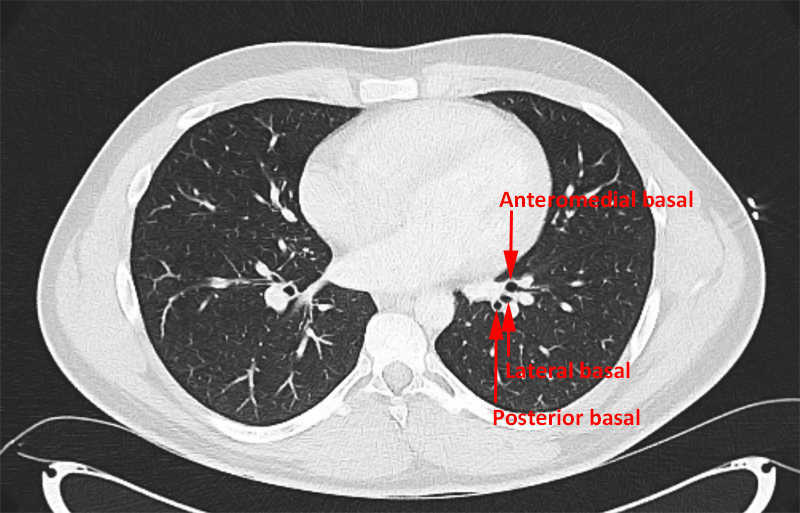

Lower lobe: Apical, posterior basal, anteromedial basal, and lateral-basal.

Left